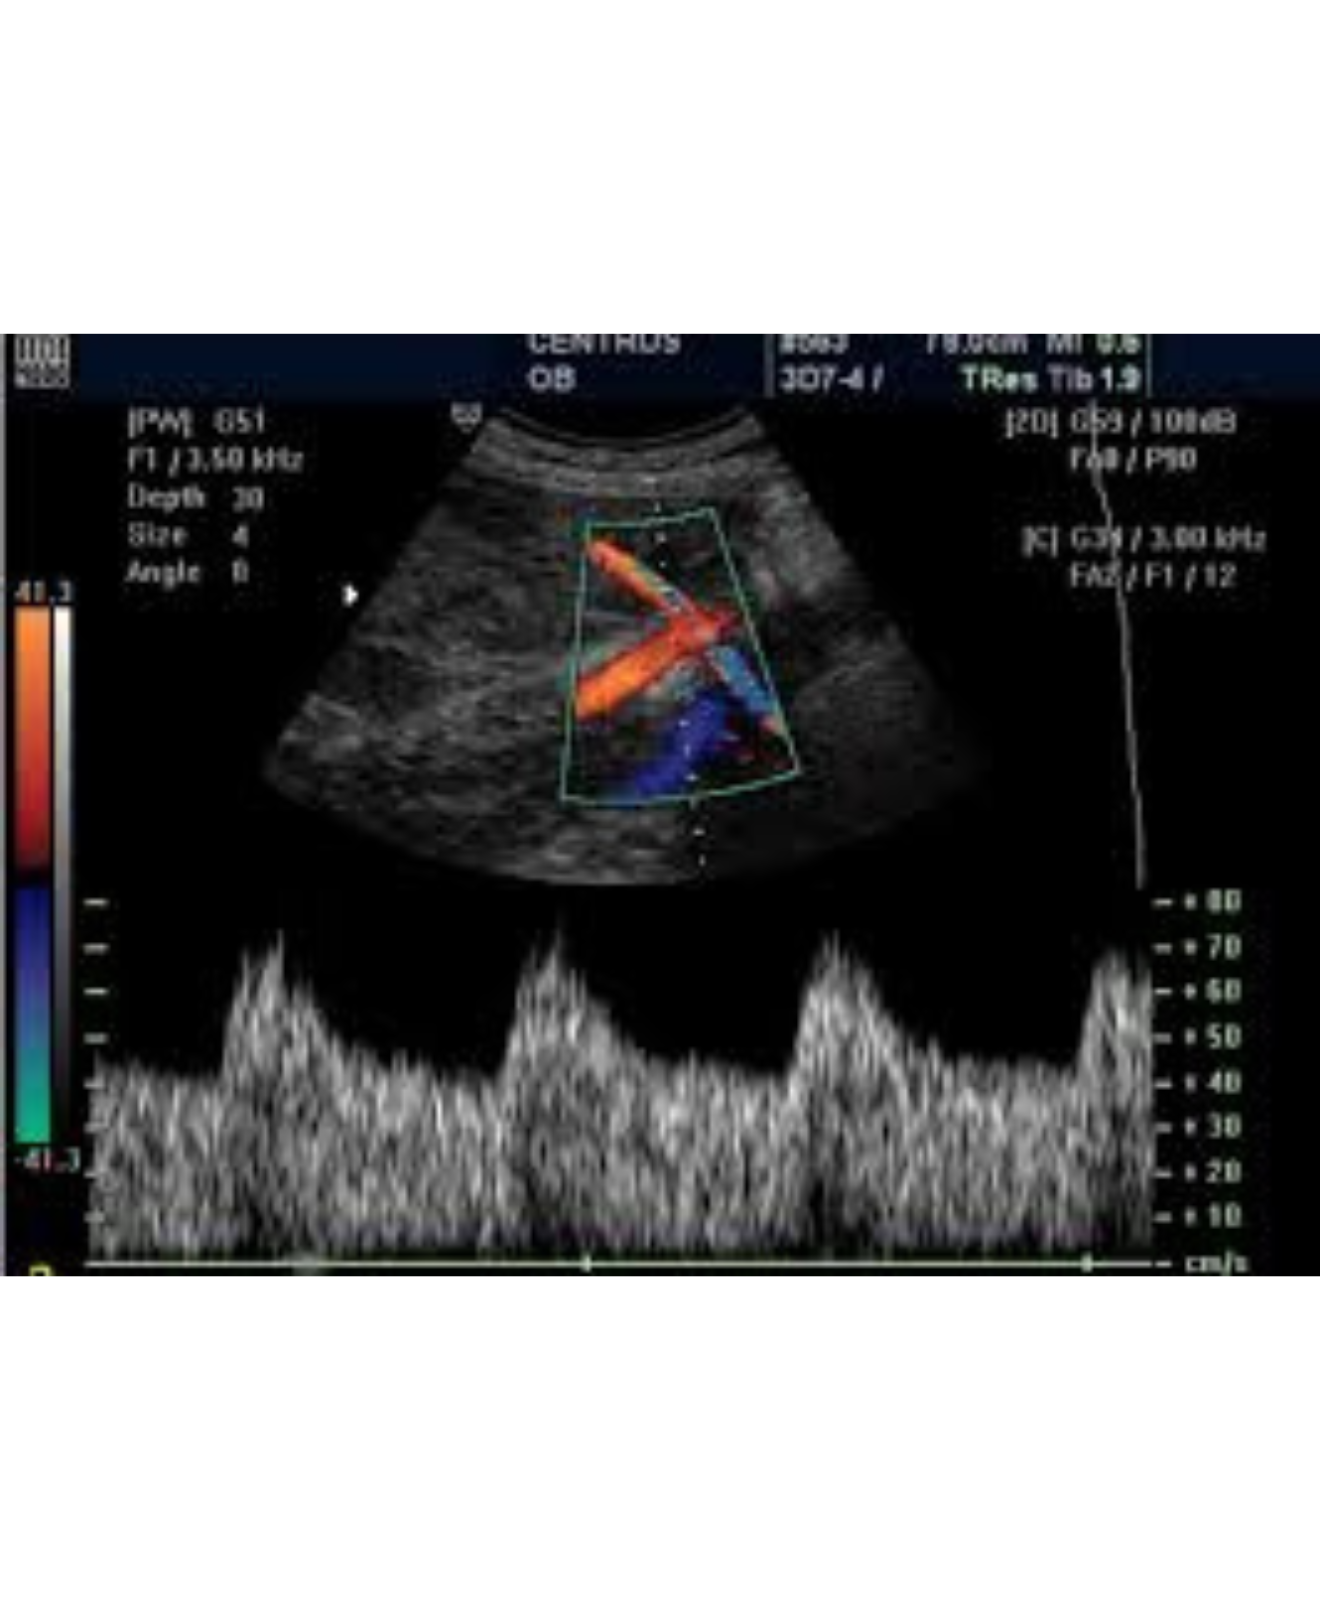

Doppler Fetal

Doppler de Arterias Uterinas

Doppler de Inserción Placentaria